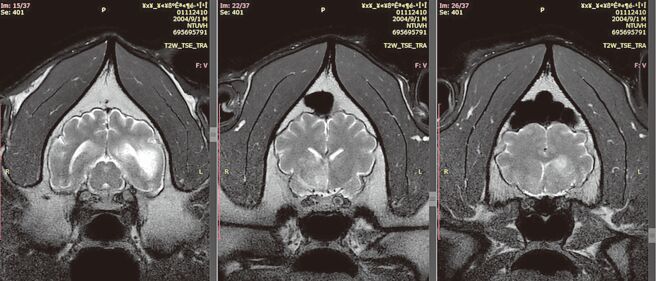

大猫熊「团团」第二次MRI检查发现病灶持续扩大(见图),台北市动物园决定改採舒缓照护方式照养。(台北市立动物园提供)

台北市立动物园大猫熊「团团」第2次MRI(磁振造影)检查结果26日出炉,病灶区域明显扩大,病程进展快速,脑部恶性肿瘤机率大幅提高。园方指出,对团团医疗、饲养方式与陆方专家保持联繫,目前评估以动物福祉为考量,将採取类似人类的安寧治疗,以舒缓疼痛症状为主,不再做任何医疗处置。

团团10月16日起出现后肢无力、食欲下降、躺着或趴着进食,休息时间变长,动物训练无法像过去一样,依照指令用鼻子碰触到目标棒。经第2次MRI检查,兽医推测,脑部恶性肿瘤机率大幅提高,但未做侵入性切片检查,仍无法百分之百确认。